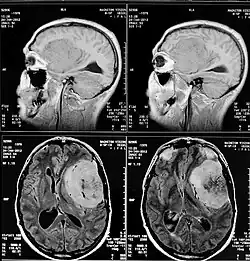

МРТ

В настоящее время МРТ с контрастным усилением является ведущим методом диагностики менингиом практически любой локализации. МРТ позволяет визуализировать васкуляризацию опухоли, степень поражения артерий и венозных синусов, а также взаимоотношения между опухолью и окружающими структурами. На нативных T1-взвешенных МРТ большинство менингиом не отличаются по интенсивности от коры головного мозга. Фиброматозные менингиомы могут быть по интенсивности и ниже коры. На T2-взвешенных МРТ менингиомы обычно повышенной интенсивности, отёк также хорошо виден на T2-взвешенных МРТ. Интенсивное контрастное усиление выявляется у 85 % менингиом. У менингиом часто встречается так называемый «дуральный хвост», участок прилежащей ТМО, интенсивно накапливающий КВ. Эта ТМО может быть как опухолево, так и реактивно изменённой. «Дуральный хвост» встречается у 65 % менингиом и только у 15 % других опухолей. Поэтому он хотя и не специфичен для менингиомы, но позволяет более точно высказаться в её пользу. Среди недостатков этого метода необходимо отметить высокую частоту ложноотрицательных результатов в отношении диагностики наличия кальцинатов и очагов кровоизлияний.

КТ

КТ с контрастированием сопровождается умеренным-выраженным гомогенным усилением в большинстве случаев. При помощи КТ диагностируются около 90 % менингиом. Главная роль КТ — демонстрация изменения костей и кальцинатов в опухоли.